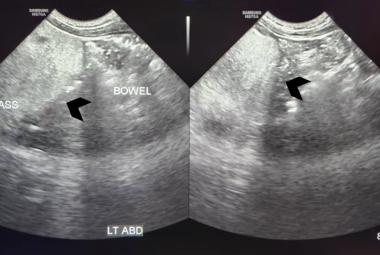

Quetiapine, an atypical antipsychotic, has various side effects, including the rare but severe complication of rhabdomyolysis. This report detailed a 32-year-old female with persistent depressive disorder (PDD) and major depressive episodes (MDE), who presented to the Emergency Department after a parasuicidal attempt involving an overdose of 8 mg of clonazepam and 4800 mg of quetiapine. She exhibited symptoms of dizziness, nausea and transient loss of consciousness, along with mild tachycardia, elevated urea and creatinine levels from her baseline. During hospitalisation, she complained of generalised body aches, especially in the lower limbs, and her creatine kinase (CK) level peaked at 10,691 IU/L. Intravenous fluid therapy led to a reduction in CK levels and normalisation of renal function, allowing for a stable discharge and psychiatric clinic follow-up. Quetiapine’s antagonism of serotonin receptors, particularly 5-HT2A, may alter muscle cell membrane permeability, contributing to elevated CK levels. Even at therapeutic doses up to 800 mg/day, quetiapine can elevate CK levels, yet routine CK testing is not standard, which can delay the diagnosis of quetiapine-induced rhabdomyolysis. This case underscores the necessity for vigilant monitoring and advocates for incorporating CK testing in the routine evaluation of quetiapine overdose, even without significant symptoms, to prevent severe complications of rhabdomyolysis.